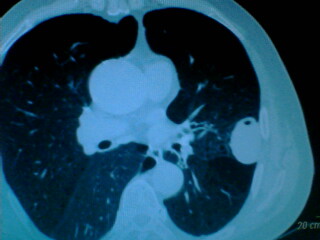

老年男性患者,右侧胸疼1月余(不是左侧),无其他症状

左肺外周类圆形病灶,其内低密度,可见液平及气影,周围肺文理见渗出样变,考虑左肺外周带肺脓肿。

考虑左肺气液囊肿

支持:左肺囊肿合并积液。

左肺舌叶胸膜下卵圆形囊性肿块,内有液-气平面,邻近胸膜无增厚,没有肺窗,周围情况显示不清,考虑胸膜下肺囊肿并感染,病人年龄较大,有胸痛应警惕其他,但神经源性肿瘤暂不考虑。

左肺囊肿合并积液